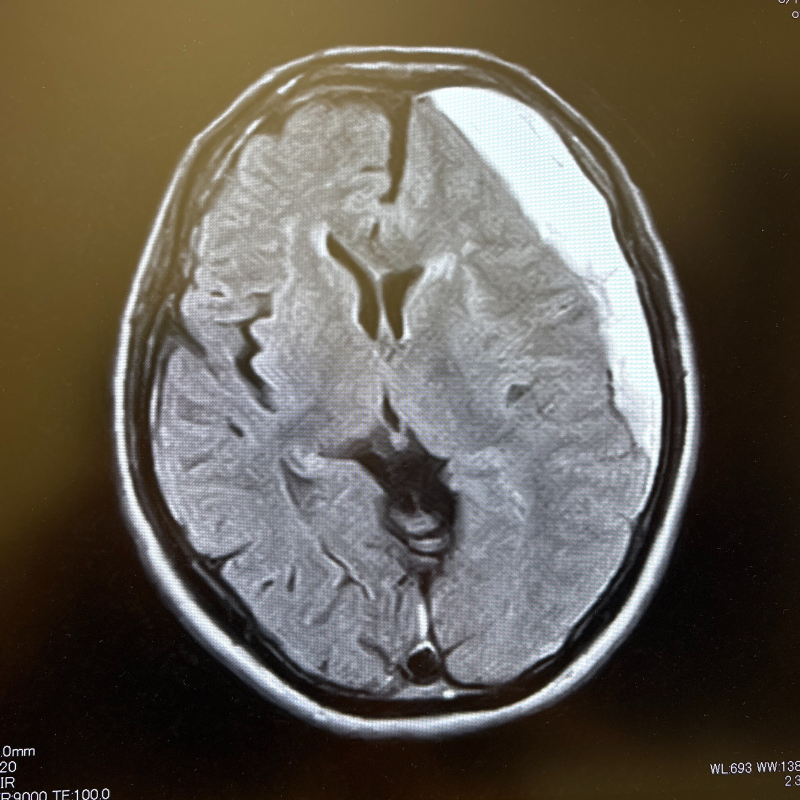

MRI画像例

下の画像は、当院で行うMRI・MRA検査で撮影できる脳の写真の一例です。

MRIでは脳の形や組織の状態を、MRAでは脳の血管の様子を詳しく確認できます。

2D画像